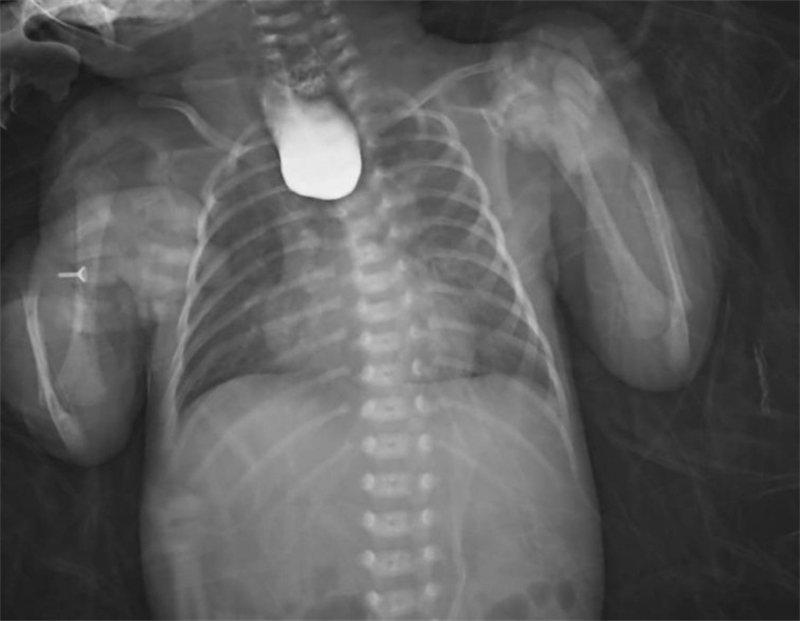

面對這一突發情況,經驗豐富的新生兒科醫生立即警覺:萱萱有可能患有少見且嚴重的新生兒先天性疾病——食管閉鎖。為了盡快明確診斷,新生兒科與小兒外科討論后,緊急聯系放射科為萱萱安排了消化道造影、CT掃描等全面檢查。最終,檢查結果明確診斷:先天性食管閉鎖Ⅲ型伴食管氣管瘺。

術后僅1天,萱萱便能通過留置胃管接受腸內營養支持。在新生兒科醫護人員的精心照料下,術后3周復查消化道造影顯示手術切口愈合良好,萱萱終于可以自己吃奶啦!